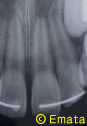

8歳・男の子のケース

夕方5時頃自転車で転倒して、前歯のおとなの歯が完全に抜け出てしまいました。(完全脱臼脱離)

根が完成されていなかったため、神経もとらずにすみました。